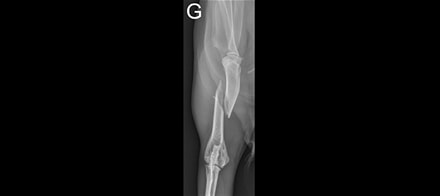

Elles sont rares mais existent dans certains cas : l'ostéopathie n'est par exemple pas indiquée dans les cas de fractures, traumatismes crâniens récents, cancers, épisodes infectieux, maladies dégénératives.